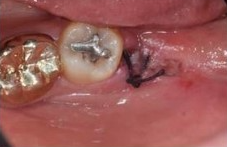

✅5일차 / 10일차

보통 일주일 정도 후부터 본격적으로

잇몸이 닫히기 시작합니다.

실밥 제거 후 발치구멍에

하얀 무언가가 얼핏 보입니다.

이는 음식물이나 염증이 아닌

정상적인 회복과정에 생기는 조직입니다.

5일차 / 10일차